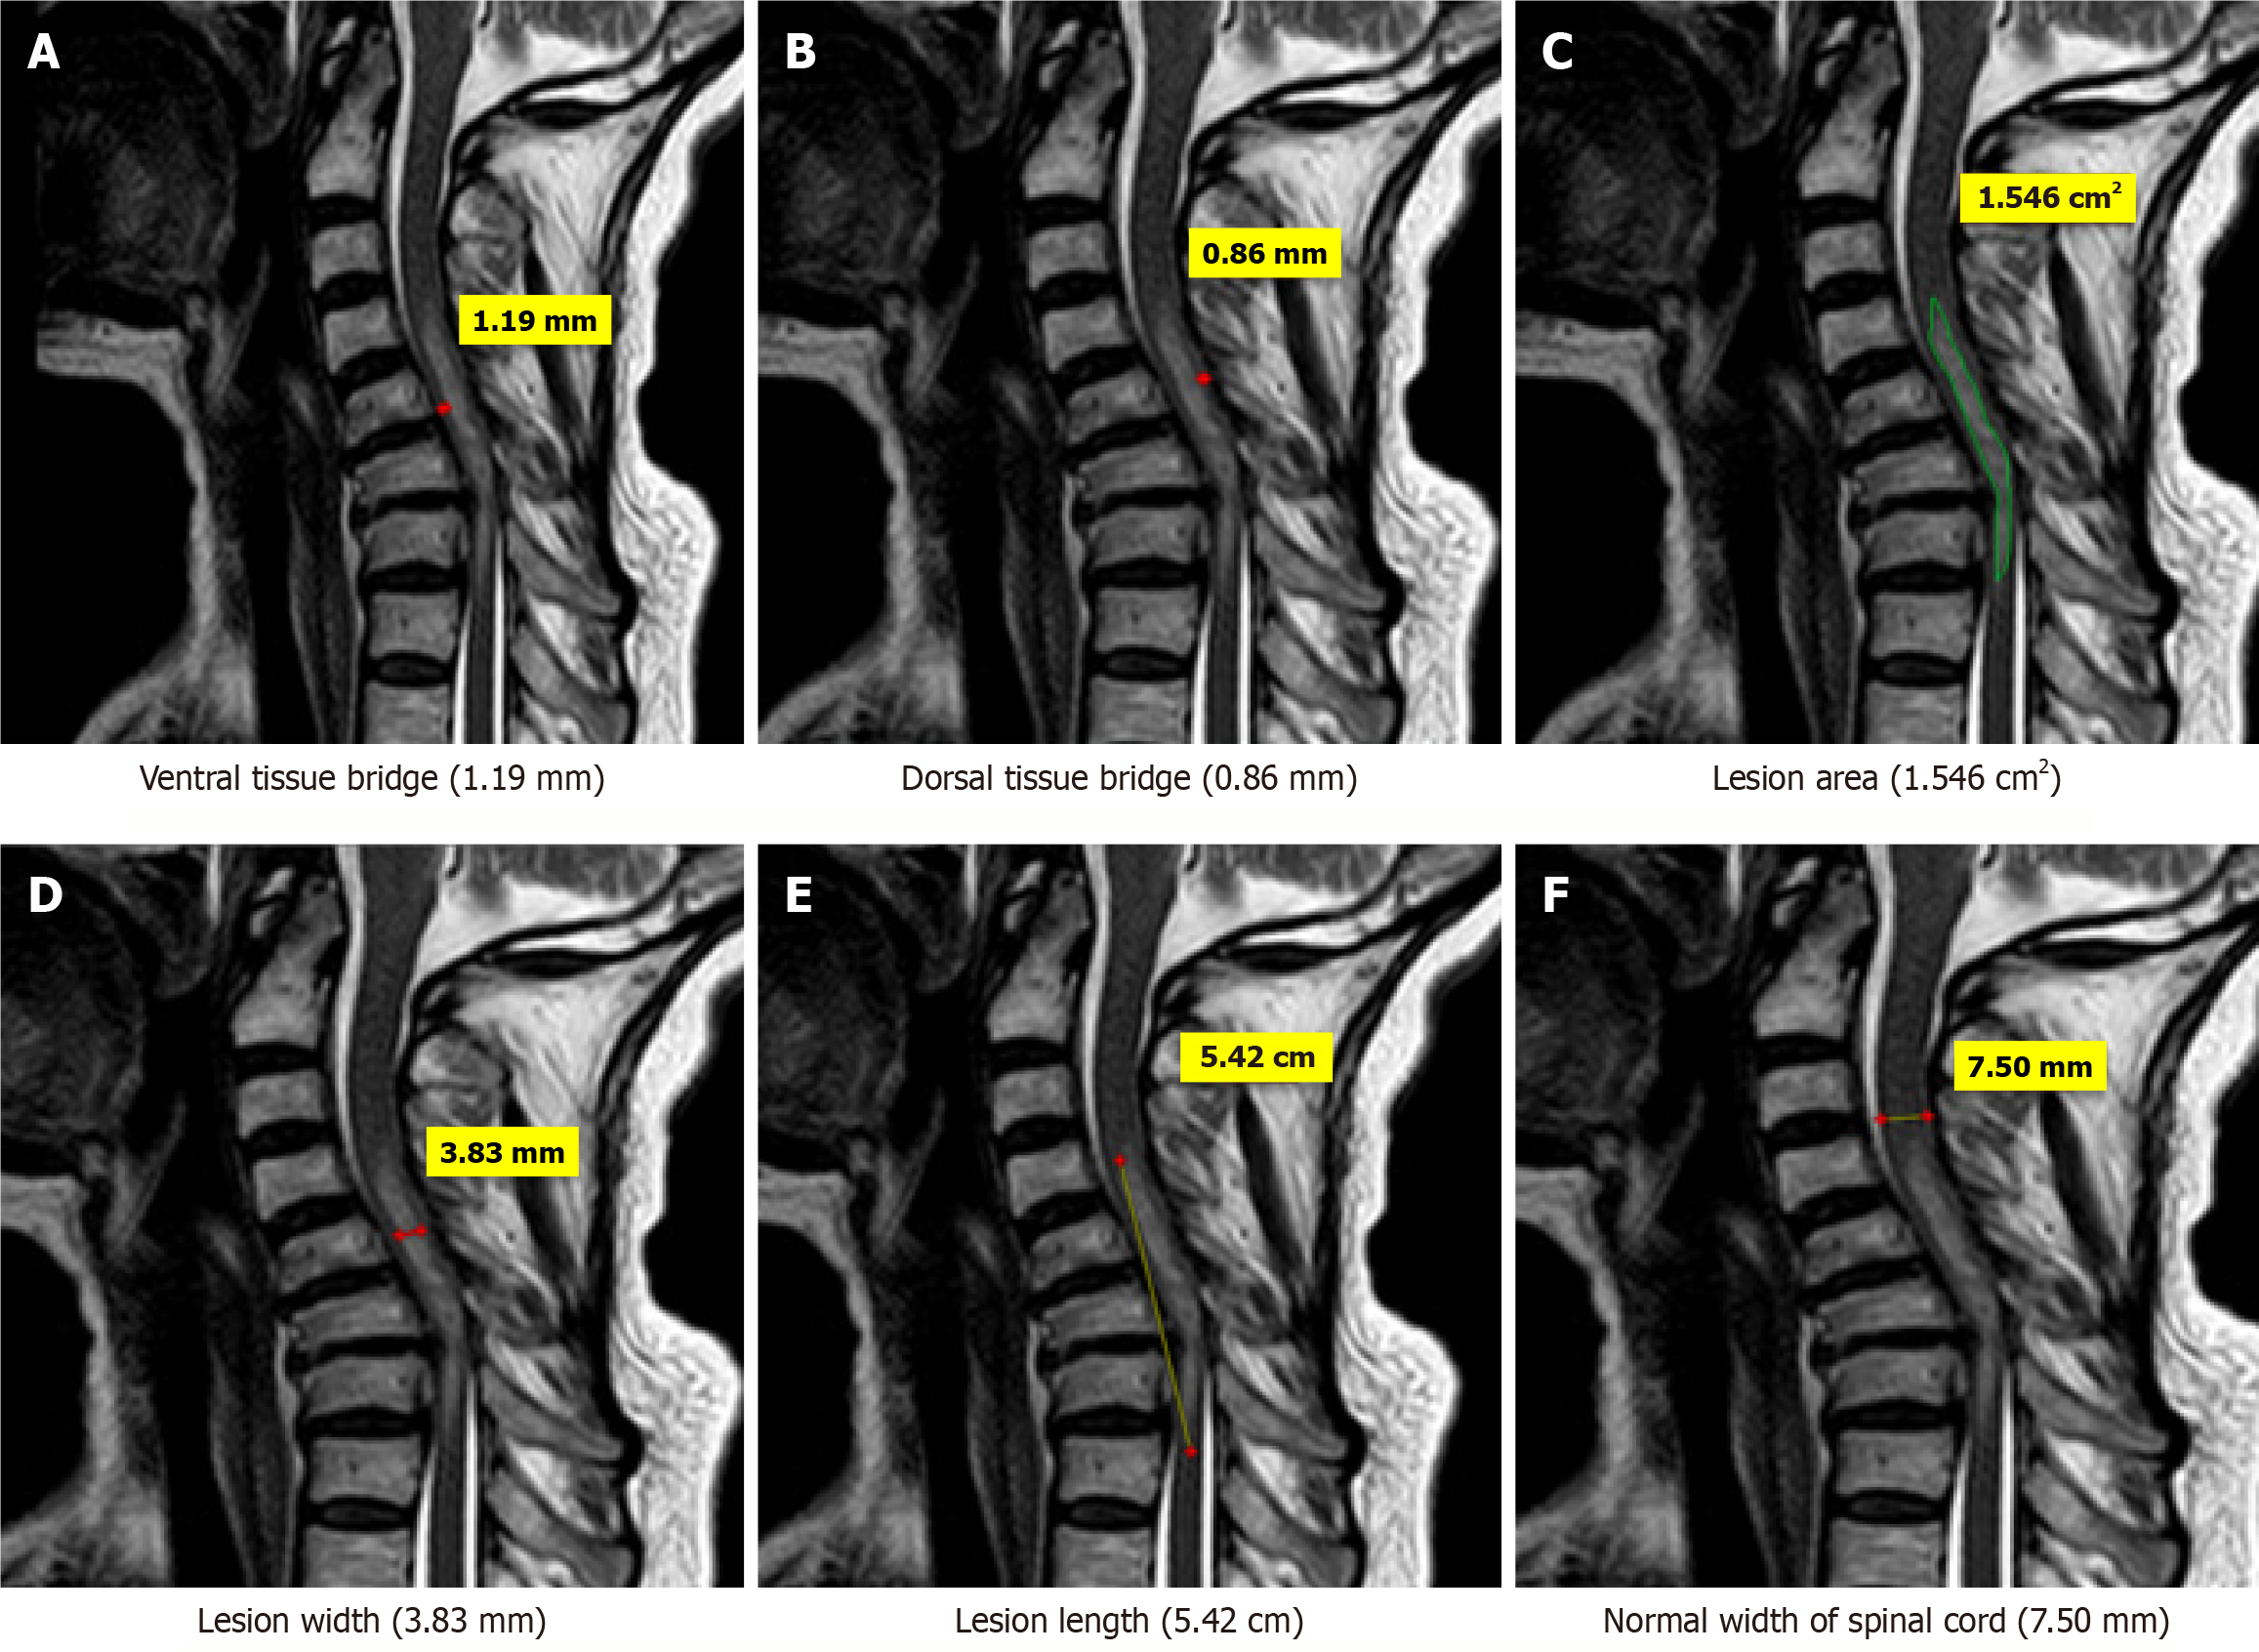

Figure 4 Magnetic resonance imaging T2-weighted sagittal images of a 48-years old patient who sustained trauma of cervical spine (C5-C6) with ASIA grade C.

A: Ventral tissue bridge(1.19mm); B: Dorsal tissue bridge (0.86 mm); C: Lesion area (1.546 cm2); D: Lesion width (3.83 mm); E: Lesion length (5.42 cm); F: Normal width of spinal cord (7.50 mm).